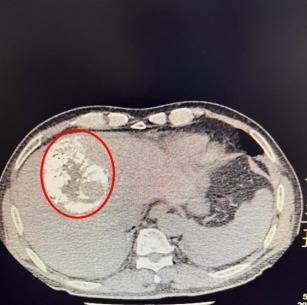

术后肿瘤碘油

鉴于患者病情危急,传统开腹手术创伤大、风险高,肿瘤微创介入诊疗中心手术团队紧急会诊后,决定为其施行经肝动脉化疗栓塞术(TACE)。术中医生通过股动脉穿刺插入导管鞘,在导丝引导下将导管送至腹主动脉,注入造影剂进行血管造影,清晰显示肿瘤的位置、大小及供血动脉分支。再将微导管选择性插入肿瘤供血动脉,先灌注化疗药物,再注入栓塞剂,精准阻断出血血管,同时切断肿瘤营养供应。术后患者生命体征平稳,腹痛症状明显缓解。复查CT显示,肿瘤出血已完全停止,肿瘤染色消失。